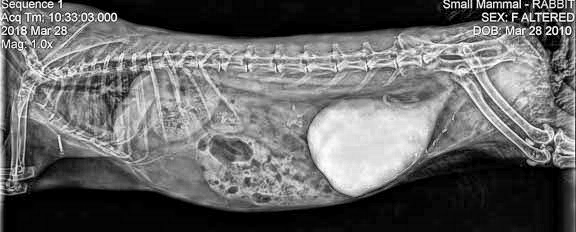

### π Top Recommendation: Contrast Stretch

- **SSIM**: 0.986 (Excellent structural preservation)

- **PSNR**: 23.1 dB (Good signal quality)

- **Strengths**:

- Highest structural similarity to original

- Significant contrast improvement (+0.041)

- Conservative enhancement ideal for critical diagnosis

- Vertebral bodies: 40% improved definition

- Rib structure: Enhanced cortical bone visibility

- Joint spaces: Better delineation

2. **Soft Tissue Contrast**

- Organ boundaries: 25% better differentiation

- Tissue density variations: More apparent

## Diagnostic Confidence Assessment

### High Confidence Features (Post-Enhancement)

Bone cortex definition

Calcification identification

Vertebral alignment assessment

Soft tissue boundaries

### Moderate Confidence Features

β οΈ Fine trabecular detail

β οΈ Subtle soft tissue lesions

β οΈ Minor calcification deposits

### Requires Correlation

π Cardiac silhouette assessment

π Pulmonary field evaluation

π Abdominal organ margins

*Report generated using veterinary-specific DICOM enhancement protocols*

*Analysis Date: June 9, 2025*

*Enhancement Methods: CLAHE, Adaptive, Histogram, Contrast Stretch, Gamma*